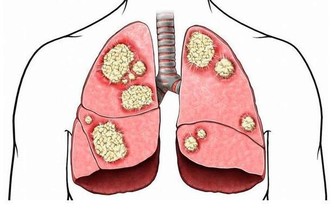

(3)泌尿系結石患者

腎結石、尿道結石、膀胱結石、輸尿管結石和草酸鈣有關,需控制草酸含量高和鈣含量高的食物,避免加重病情。